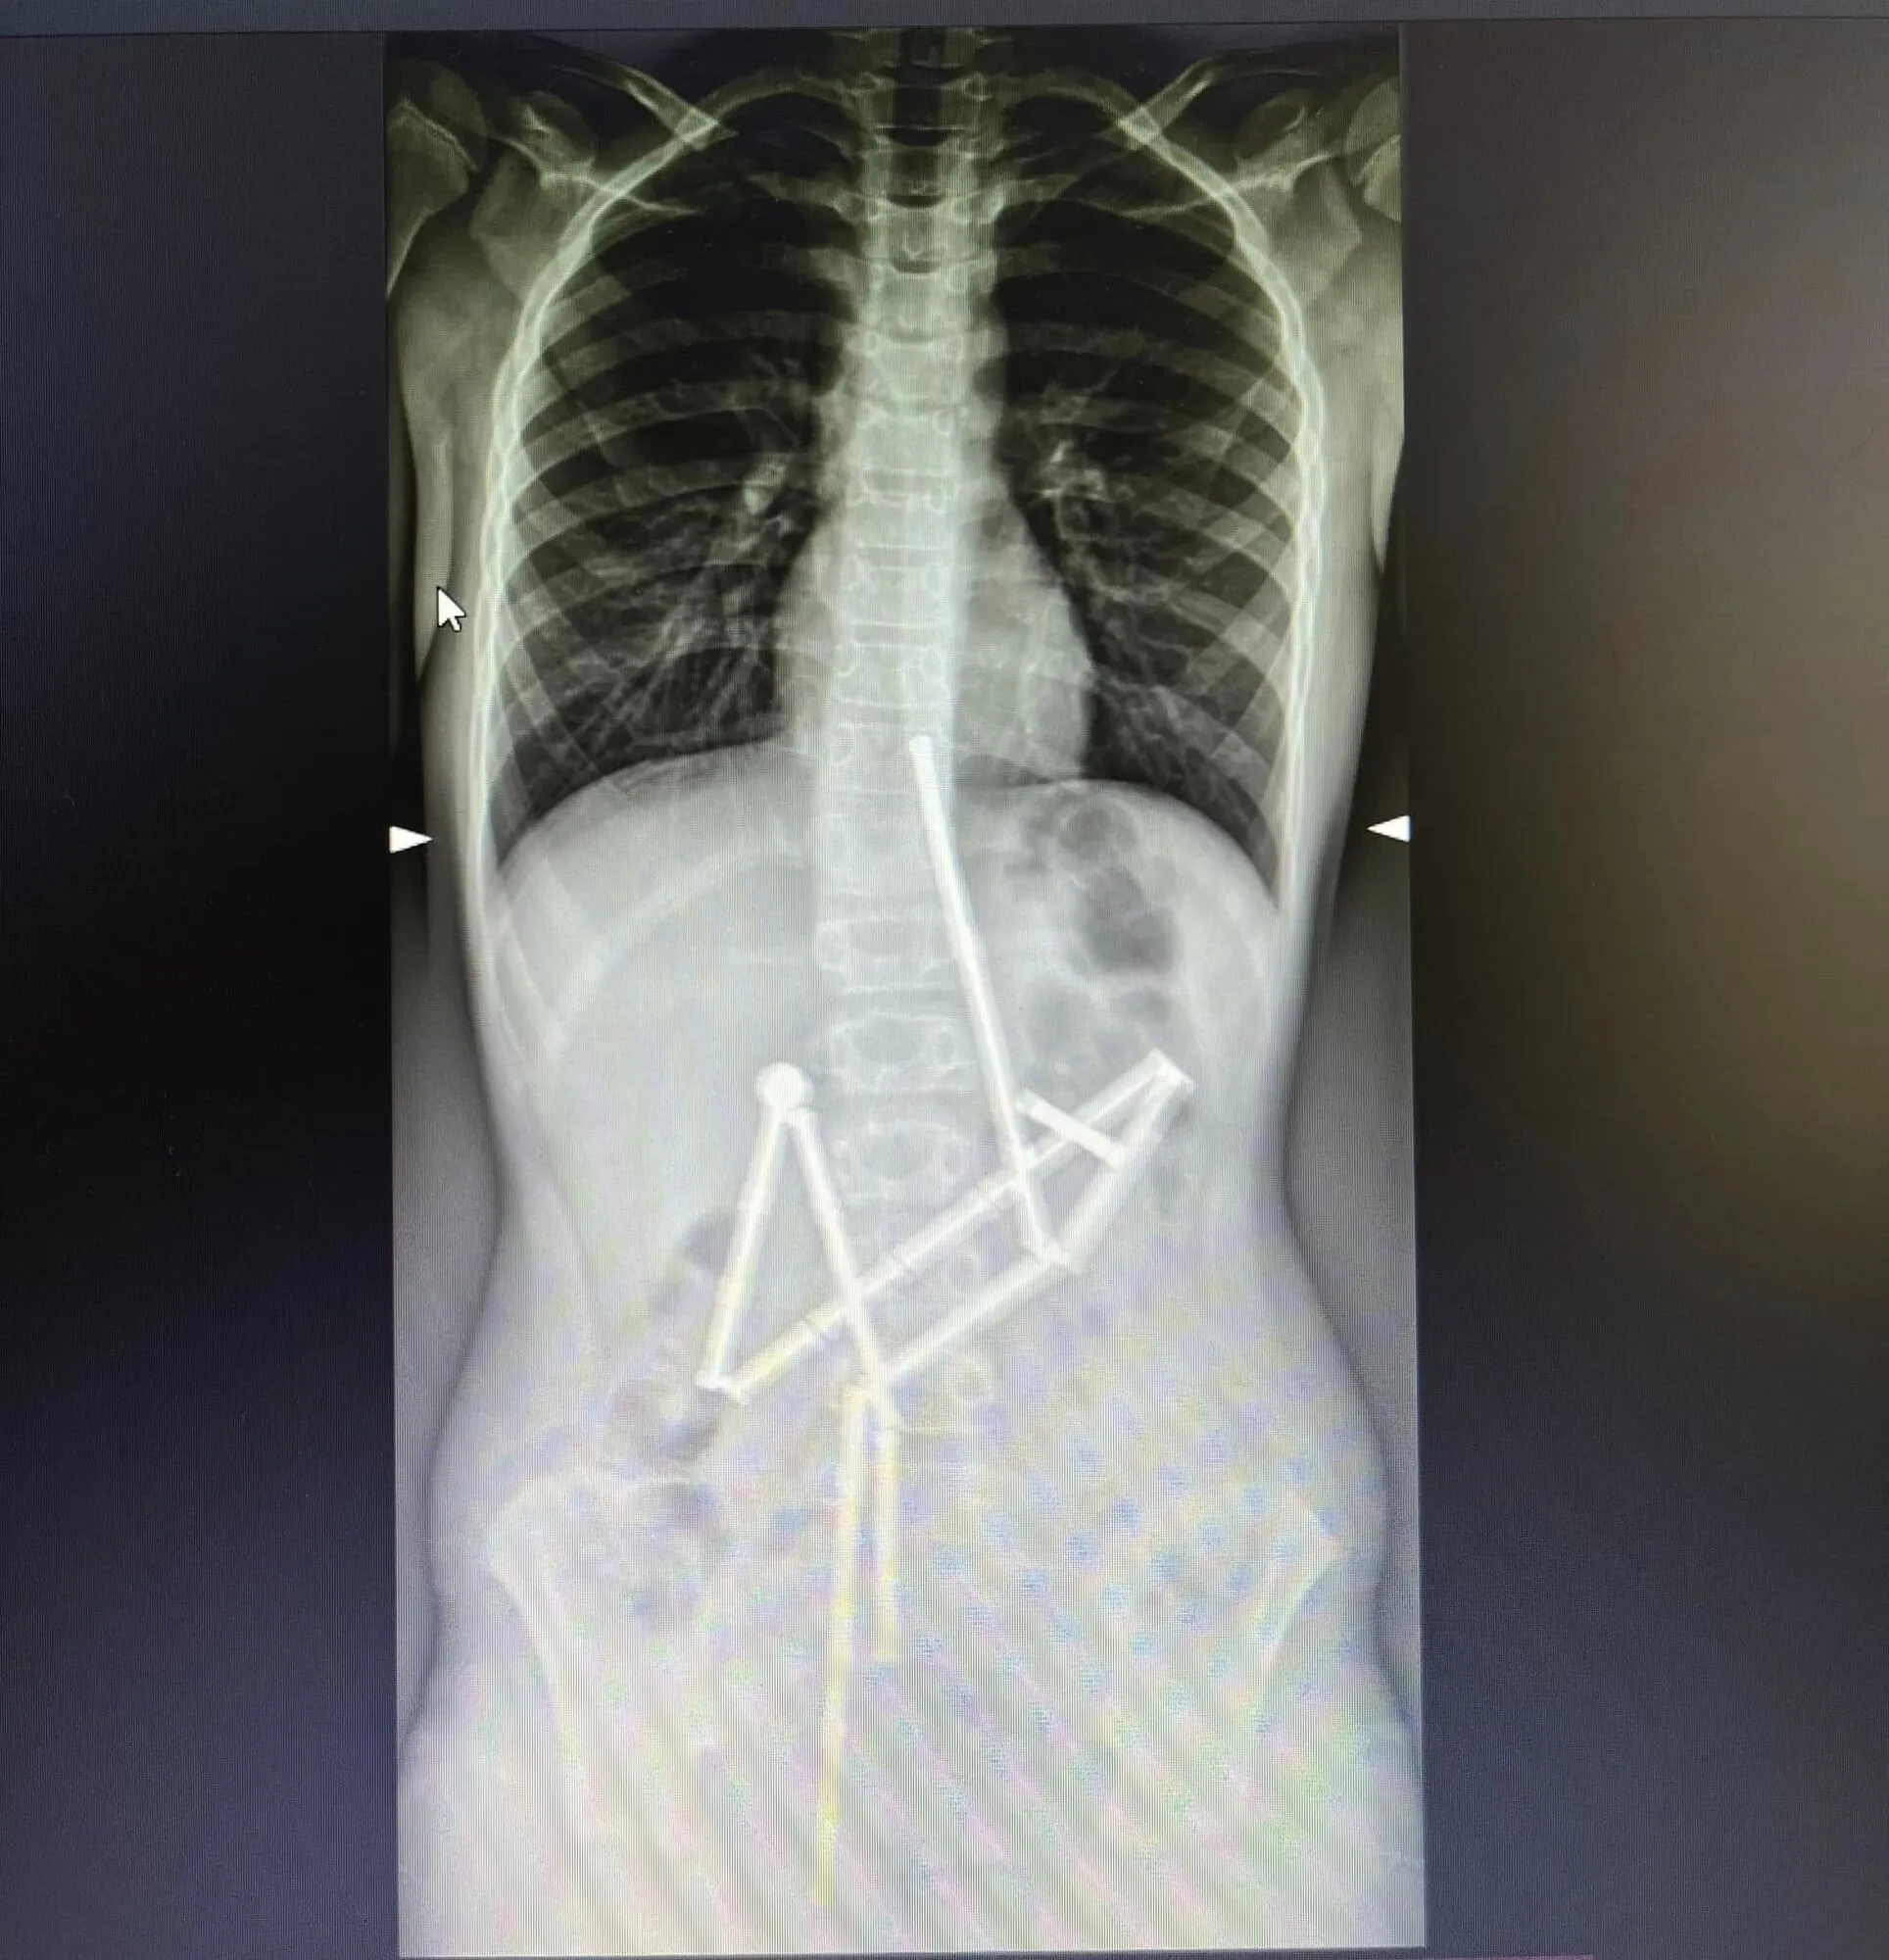

По словам врачей, к ним обратились родители мальчика, жаловавшегося на боль в животе. Уже на первом рентген-снимке специалисты увидели наличие в пищеварительном канале целой группы посторонних тел, в которых удалось узнать магнитный конструктор. 20 магнитов находились в разных частях желудочно-кишечного тракта, однако были соединены между собой.

Медики приняли решение о безотлагательном проведении операции, потому что магниты, в отличие от других посторонних тел, которые могут проглотить дети, притягиваются друг к другу и могут защемить ткани. Как следствие – возникают зоны некроза (омертвение), перфорации полых органов, желудочно-кишечные непроходимости и т.д.

"Бригада анестезиологов как можно быстрее инициировала предоперационную подготовку и введение в наркоз. Первой к работе стала команда специалистов отделения эндоскопии. Они провели исследование слизистых оболочек пищевода, желудка и двенадцатиперстной кишки и оценили состояние верхних отделов пищеварительного тракта, желудка и двенадцатиперстной кишки и оценили состояние верхних отделов пищеварительного тракта, нашли проглоченные объекты, которые были соединены между собой. Медикам удалось захватить первый магнит и вытащить его вместе с цепочкой из 18 элементов конструктора", – уточнили в пресс-службе.

Чтобы получить последний магнит, мальчику провели операцию, во время которой также было обнаружено 5 перфоративных отверстий – их закрыли. Благодаря таланту и профессионализму медиков ребенок был спасен. В настоящее время он проходит послеоперационный курс лечения и реабилитации.